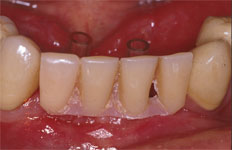

El primer paso consiste en colocar pilares protésicos y comprobar radiográficamente su correcto asentamiento (generalmente UCLA metálicos o bien existen sistemas que presentan cilindros plásticos para la confección de provisionales). Se confecciona acrílico autopolimerizable y al llegar a su estado plástico se realiza un dado que es adaptado sobre el pilar protésico. En boca y ayudado por una espátula se va dando forma. Al polimerizar se retira el provisional de la boca y con puntas montadas se eliminan los excesos de acrílico. Es importante que la remoción del acrílico sea relizada con puntas de corte fino que dejan una superficie más lisa favoreciendo una textura final más uniforme. Si se necesita hacer retoques se realizan por la técnica del pincel. Los ajustes oclusales son realizados con papel de articular y fresas esféricas. El 1/3 cervical debe tener un acabado con puntas de granos extras finos y gomas. Una vez terminado el acabado el provisional debe ser pulido con piedra pómez y agua con cepillos y ruedas de fieltro, hasta lograr una superficie de textura brillante.    Figuras 1, 2 y 3

EPÍGRAFES Figuras 1, 2 y 3: Método directo "a mano alzada" para confeccionar un contorno gingival correcto. Figuras 4, 5, 6 y 7: Método directo utilizando diente stock para permitir la remodelación ósea en implante "corto". Figuras 8, 9 y 10: Método directo empleando dientes de la prótesis removible del paciente. Figuras 11 y 12: Método directo empleando dientes de la prótesis removible del paciente utilizando cilindros plásticos. Figuras 13, 14 y 15: Método hibrido. Figuras 16, 17, 18, 19, 20: Método híbrido con el objeto de parcializar el tratamiento. Figuras 21, 22,23 y 24: Método indirecto con el propósito de brindar una solución económica y estética.